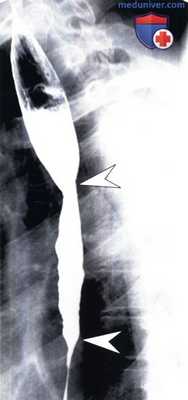

Такие проявления более характерны для рефлюкс-эзофагита, чем для опухоли. Рефлюкс-эзофагит с фокальной стриктурой у женщины 63 лет.

(а) Выявлены фокальная стриктура (стрелка) в дистальном отделе пищевода и расширение проксимального отдела с утолщением складок (указатели).

(б) При рентгенографии с двойным контрастированием четко визуализирована фокальная стриктура пищевода (стрелка).

Идиопатический эозинофильный эзофагит у мужчины 21 года.

На рентгенограмме выявлено диффузное неравномерное сужение просвета (указатели) в нижней половине пищевода с дилатацией в проксимальном отделе и нарушением пассажа.